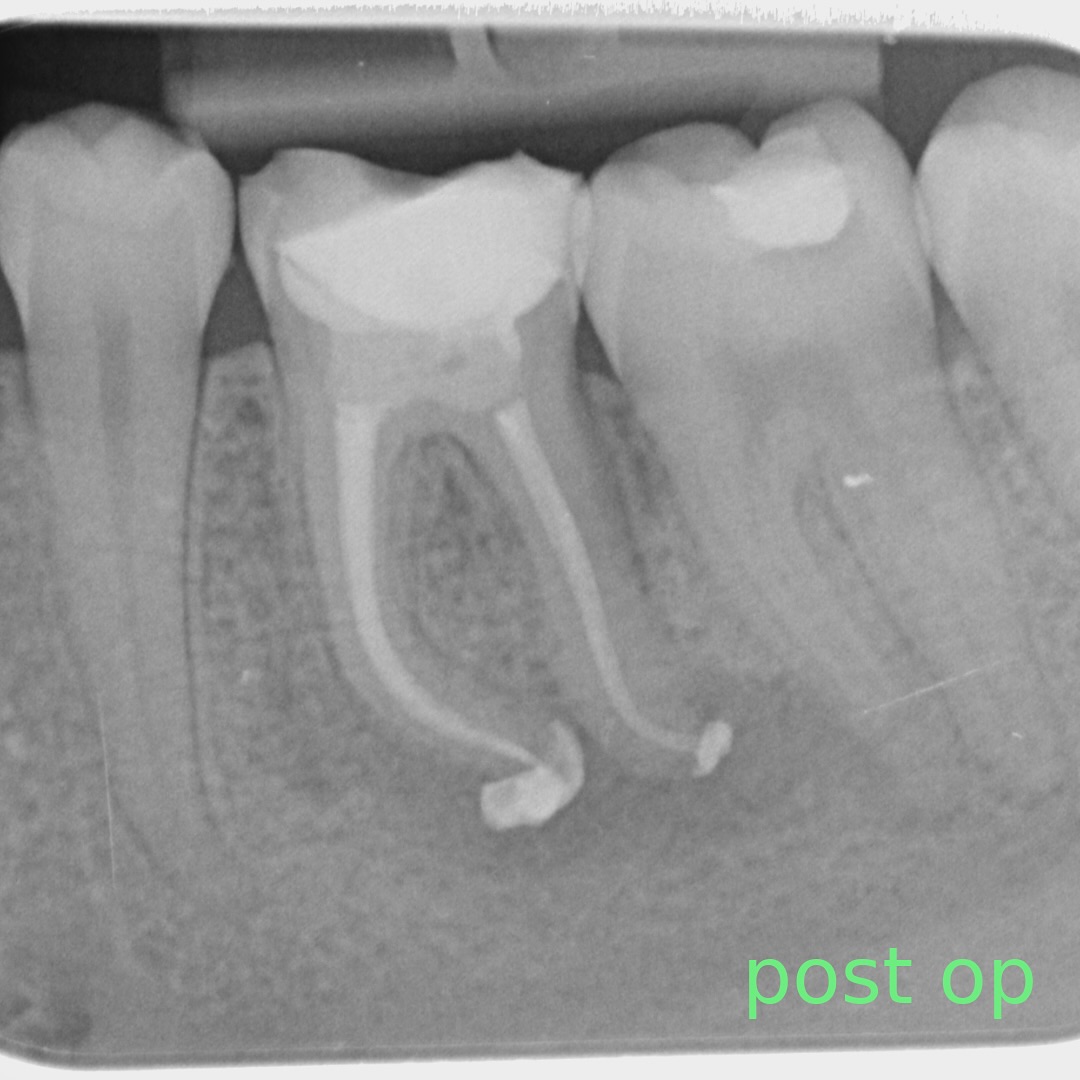

A comprehensive, non-specialist referral service for dental patients requiring affordable Endodontic treatment

Information regarding our services can be found here